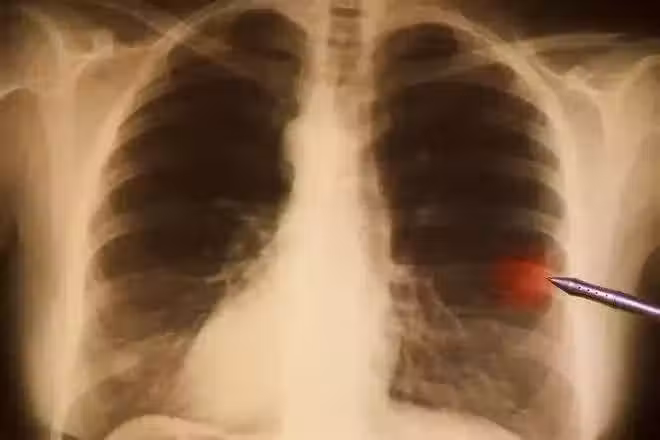

2007年,寫完《中國新革命》,他 突然 暈倒 ,妻子陪著去做檢查,結果發現是肺癌晚期。

全身多處有陰影,癌細胞已經向各處擴散,醫生說 要做好思想準備,可能活不過三個月。